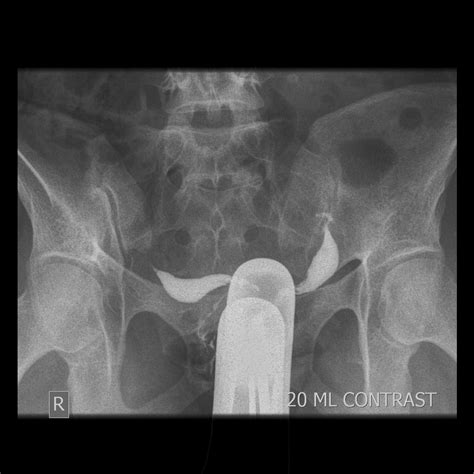

When individuals search for Didelphic Uterus Pictures, they are often seeking clarity on how their anatomy differs from the standard uterine structure. Medical imagery, such as MRIs, ultrasounds, and 3D pelvic reconstructions, provides the best visual representation of this double structure. Unlike a bicornuate uterus—where the two horns are connected—the Didelphic uterus consists of two completely independent units.

Viewing these medical images helps patients understand why they may experience certain symptoms. For example, the presence of two cervices is a hallmark feature visible in clinical scans. Understanding these visuals can help patients communicate more effectively with their gynecologists during consultations.

| Hysterosalpingography | Used to observe the shape of the uterine cavities using dye. |